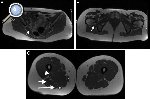

Figura 2. Músculos inervados por el nervio ciático. A) Músculo piriforme (flecha). B) Músculo cuadrado femoral (flecha). C) Músculos grácil (asterisco pequeño), cabeza corta del bíceps femoral (cabeza de flecha), cabeza larga del bíceps (flecha corta), semimembranoso (asterisco grande) y semitendinoso (flecha larga).